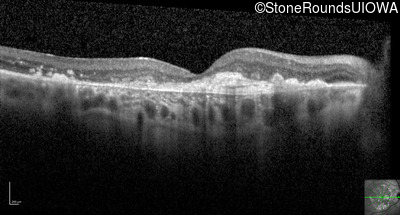

Optical Coherence Tomography - Right - 20/200 +1

Exemplar / OCT Stack